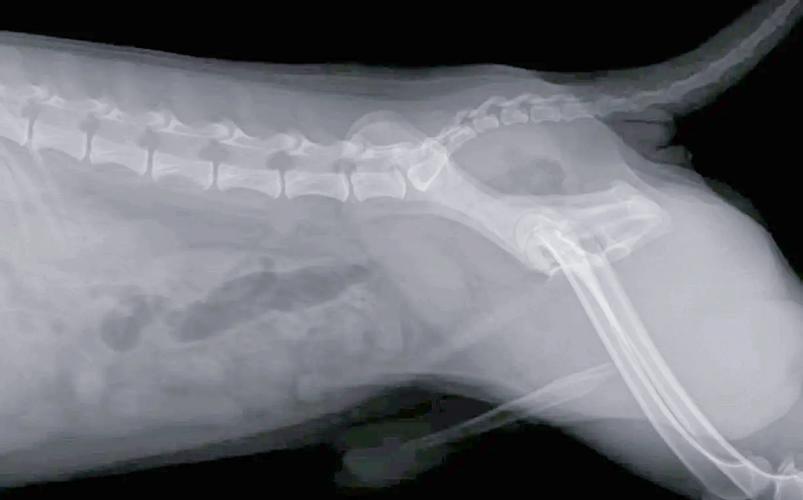

狗狗后腿骨折治疗费用大概多少

总费用估算:综合以上各项费用,狗狗后腿骨折手术的总费用可能在数千元至万元不等。如用户所述,其狗狗因骨折伴有碎骨而进行了内固定手术,前前后后已经花费了5000元左右,并且还有后续的消炎药和住院费用。注意:以上费用仅供借鉴,具体费用还需根据狗狗的实际情况、所在地区的医疗水平和医院收费标准来确定。

手术费用:手术费用会根据骨折的类型和严重程度而有所不同。简单骨折的修复手术费用大约在1000至2000元,而复杂骨折的手术费用可能会更高。 康复费用:康复治疗是骨折恢复过程中的关键环节。费用通常在几百元到一千元之间,具体取决于治疗次数和采用的治疗方法。

先带去医院拍片子,80『1』00一张。如果不严重只需要做外固定大概几百元,凡是如果狗狗骨折严重的话,可能要做手术,手术的话一般就是内固定,但是差不多在5000『6』000左右,但是也是需要根据狗狗的体型以及医院的价位来计算。先确定有没有内伤,再考虑手术的问题。

拆线或复查每次约100『2』00元。 若需物理康复(如激光治疗),单次费用约150『3』00元。建议直接联系当地宠物医院,提供狗狗的体重、骨折部位及X光片,可获取准确报价。部分医院支持分期付款。